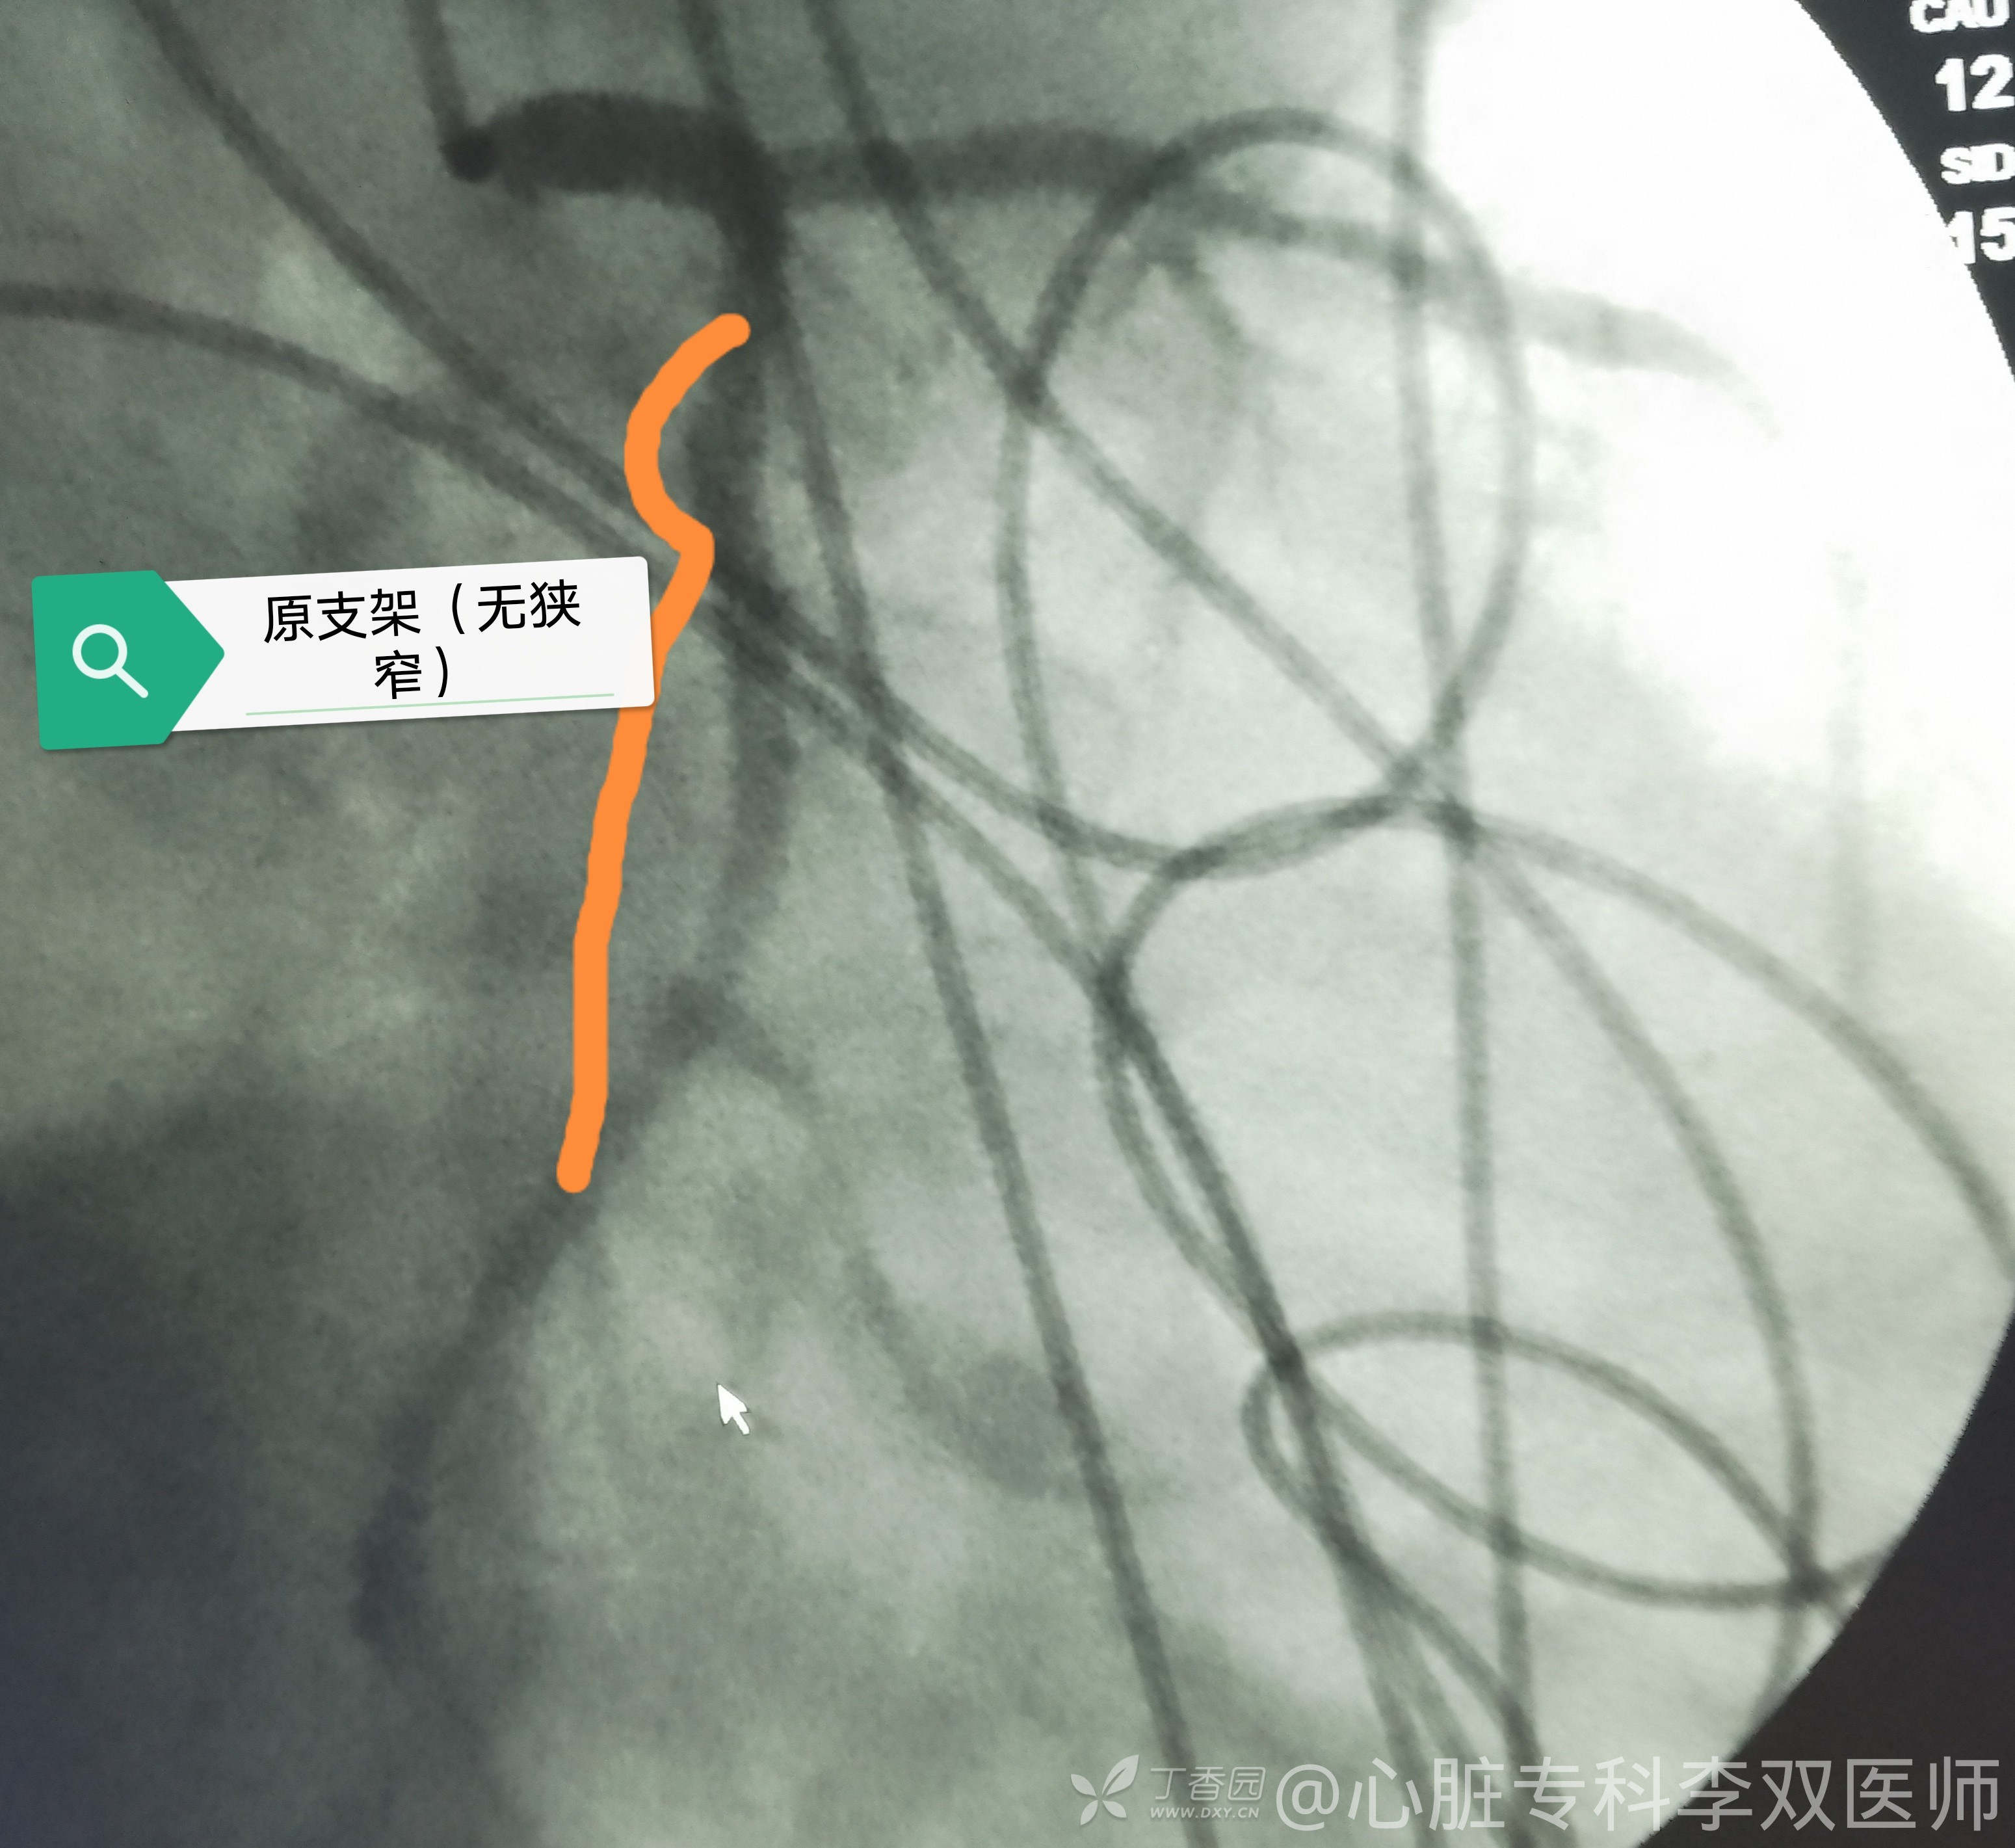

住院后复查了增强CT情况不太好。造影支架内再狭窄,也是个临界病变,就不处理了,马上去查肺去。